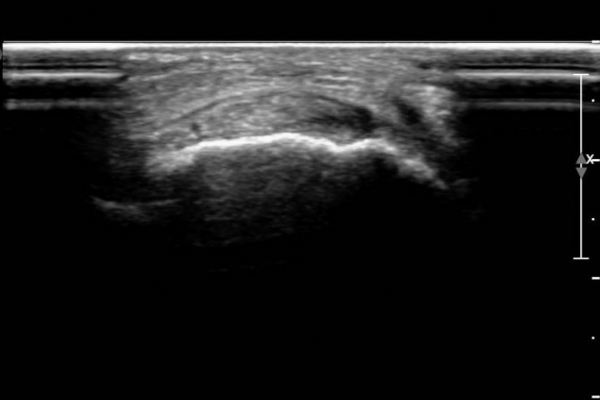

ŽÃËÀÚ¸¦ ¾à°£ ¹ß¹Ù´ÚÃøÀ¸·Î À̵¿ÇÏ´Ï ¼³Çü°ñ ºÎÂøºÎ°ÇÀÇ Àú¿¡ÄÚ º´º¯ÀÌ ¶Ñ·ÈÇÏ´Ù(»çÁø 3, 4).

Àü°æ°ñ°Ç Ⱦ´Ü¸é°Ë»ç¿¡¼­ Á»´õ ¹ß µîÃøÀ¸·Î À§Ä¡ÇÏ´Â Á¦1ÁßÁ·°ñºÎÂøºÎ °ÇÀº °í¿¡ÄÚ·Î Á¤»óÀûÀÎ ¾ç»óÀ¸·Î

°üÂûµÇ³ª Á»´õ ³»Ãø ¹Ù´ÚÃø¿¡ À§Ä¡ÇÏ´Â ¼³Çü°ñ ºÎÂøºÎ °ÇÀÇ Àú¿¡ÄÚ º´º¯ÀÌ °üÂûµÈ´Ù(»çÁø 5,  6).